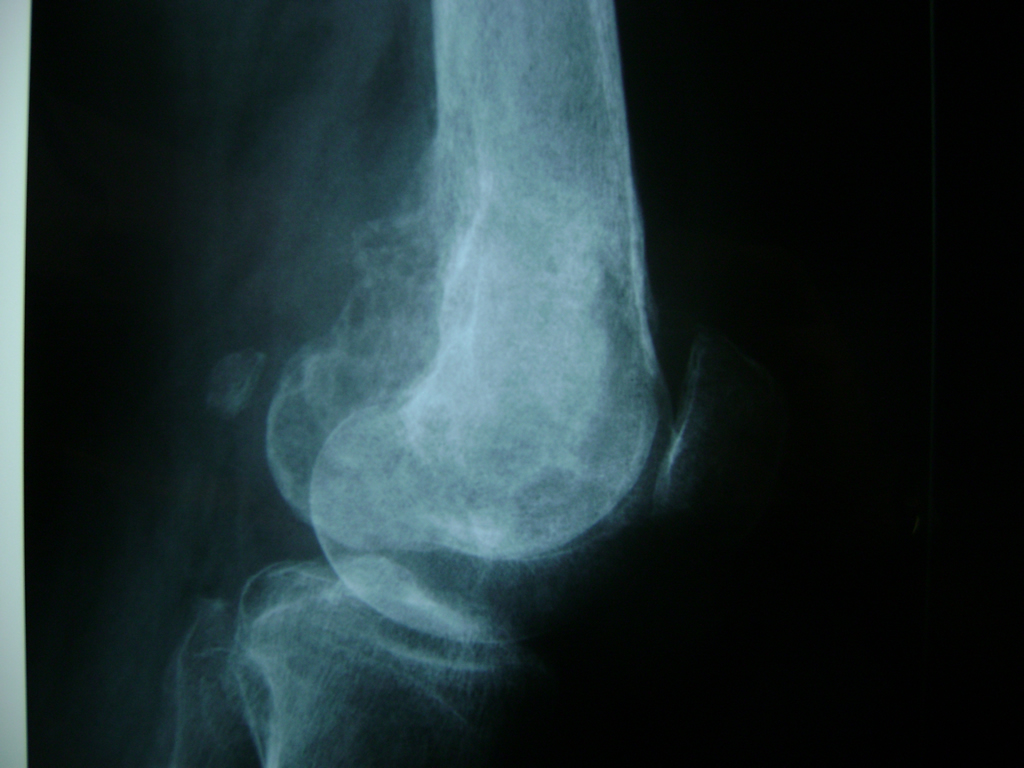

Fémur - Rodilla

La artroscopia de rodilla es un cirugía en el cual la estructura interna de la articulación es examinada ya sea para realizar un diagnostico o para realizar un tratamiento, este procedimiento se realiza utilizando un instrumento parecido a un pequeño tubo llamado artroscopio.